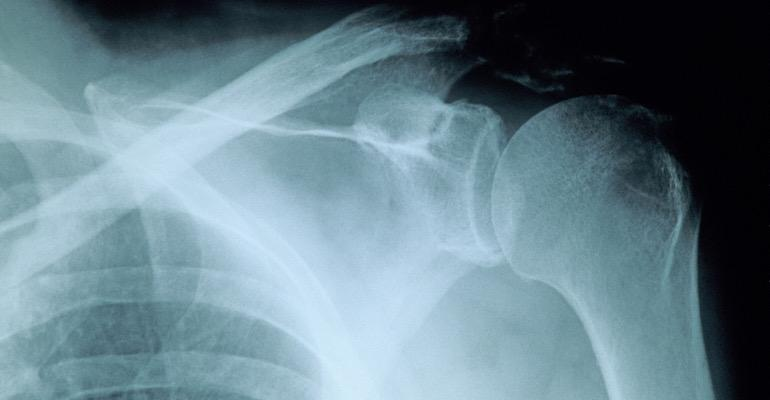

An Atlanta-based startup is changing the way a patient’s x-rays are taken. Oxos Medical has developed Micro C, a point-of-care X-ray technology, which has been cleared by FDA.

Traditional radiology solutions, such as C-Arms, the machines used for fluoroscopic imaging during procedures, are well known for their limitations in image quality and high radiation exposure.